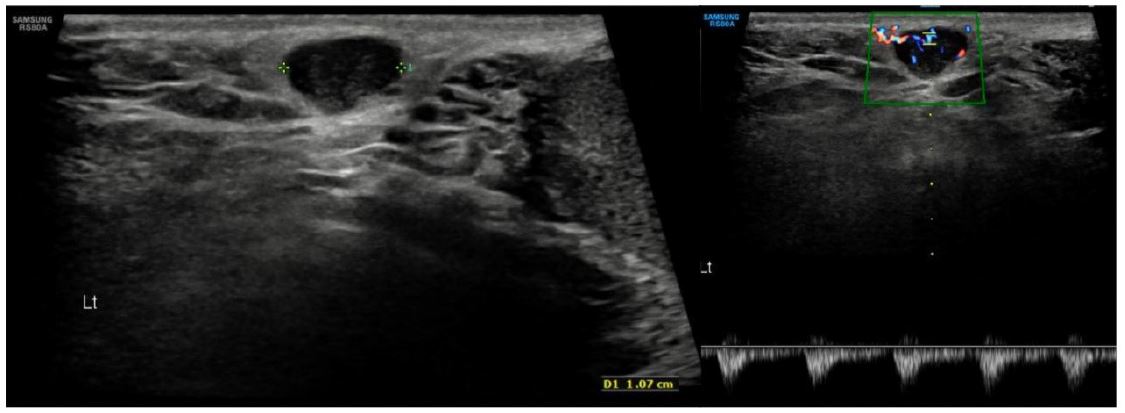

At the first reassessment after four cycles of selpercatinib, a response was observed, marked by a significant reduction in tumor mass and disease stability confirmed by subsequent imaging (Figures 4 & 5).

Figure 4: The left image depicts the lung lesion at diagnosis (May 2023); the central image shows the lesion prior to selpercatinib initiation (January 2024); and the right image illustrates the lesion after 13 cycles of selpercatinib (January 2025), demonstrating a near-complete response.